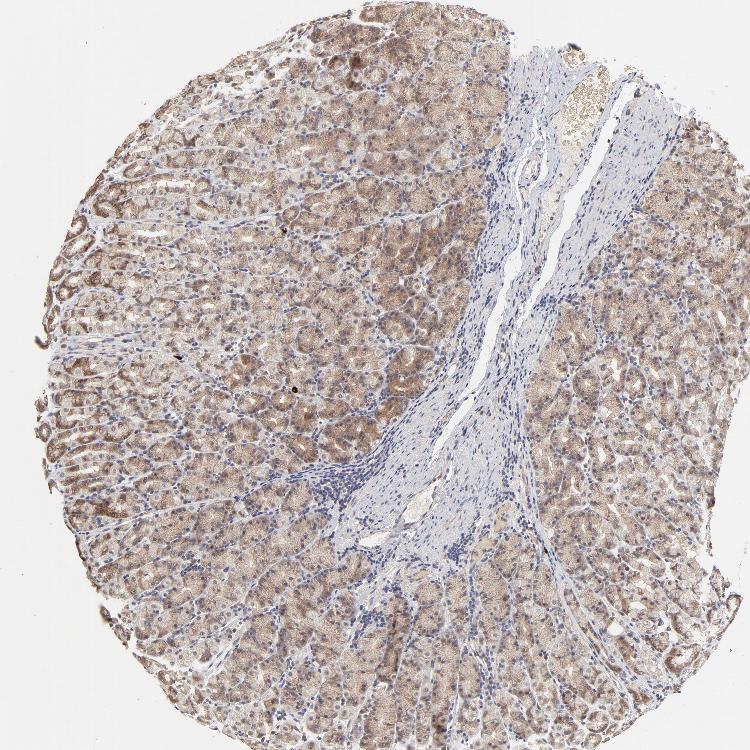

STOMACH 1 - Antibody stainingi

Antibody staining in the annotated cell types in the current human tissue is reported as not detected, low, medium, or high, based on conventional immunohistochemistry profiling in selected tissues. This score is based on the combination of the staining intensity and fraction of stained cells.

Each image is clickable and will lead to virtual microscopy that enables deeper exploration of all samples and also displays staining intensity scores, fraction scores and subcellular localization as well as patient and tissue information for each sample.

Antibody HPA002861

Glandular cells Medium